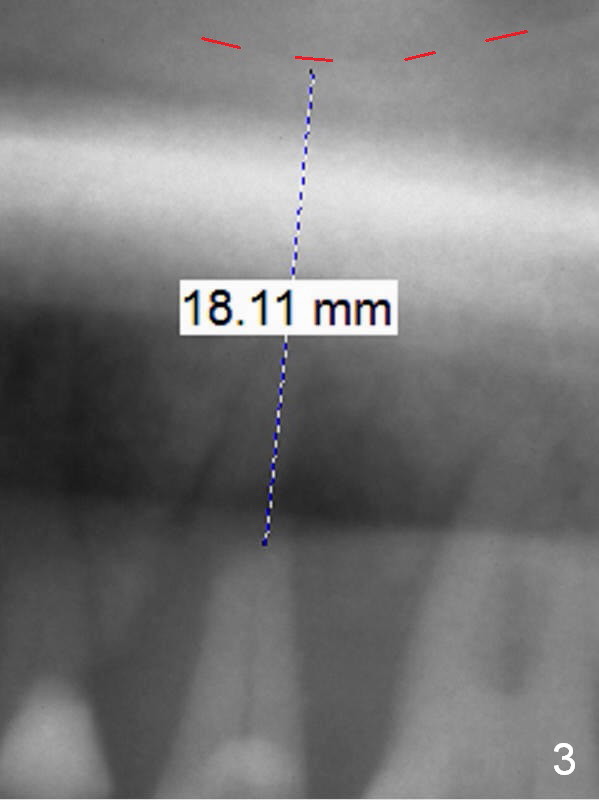

A 59-year-old man (smoker) is concerned about his oral conditions (periodontitis, partial edentulism (loss of #15 and #31) and #13 root fracture (*, possibly bruxism (sufficient clearance for provisional)), Fig.1,2) and wants to have a change. First SRP will be done on the left side with #13 extraction (Metronidazole, large socket (bone loss), large gauze) and immediate implant. Considering severe bone loss and bone height (sinus floor: red dashed line in Fig.2), a long narrow UF implant will be placed away from the lesion (most likely palatal if the buccal plate is lost) and deep with possible using 5-mm cuff abutment. To further prevent periimplantitis, smoke reduction is to be enforced preop (ask the patient about the cessation with care immediately prior to surgery) and PRF membranes (2-3) will be placed over the defective plate and into the sinus if needed. Also prepare sufficient amount of bone graft (especially to be placed mesial to #14).